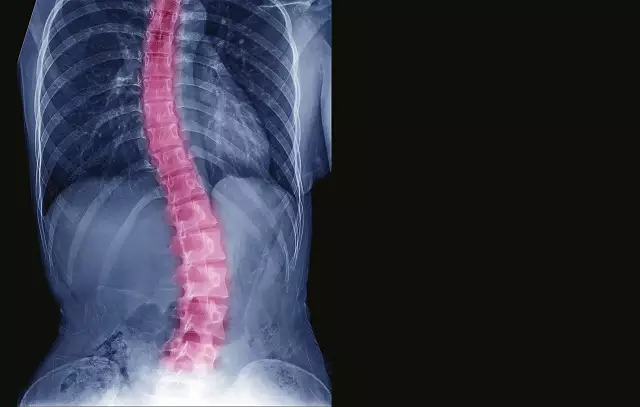

Apesar de 6 milhões de brasileiros conviverem com a escoliose, a doença ainda é desconhecida pela população e nem sempre é diagnosticada precocemente, um obstáculo já que os médicos afirmam que quanto mais cedo a descoberta da enfermidade, maior é a probabilidade de sucesso do tratamento não operatório.

Existem diferentes tipos de escoliose, porém a mais incidente é a idiopática cuja principal característica é o surgimento no início da fase de puberdade. Como o próprio nome já diz, a escoliose idiopática não tem causas definidas, mas sabe-se da forte influência genética, já que a incidência é alta em parentes diretos de pacientes com escoliose e ocorre com maior prevalência em adolescentes do sexo feminino.

Conjunto de ossos articulados que formam o eixo de sustentação do corpo, a coluna vertebral não tem como função apenas a proteção da medula espinhal, do sistema nervoso central, como possibilita agilidade e movimento dos membros, viabilidade e manutenção da postura ereta, proteção aos órgãos internos, além de absorção e dissipação de choques mecânicos e pressão gravitacional.

Mas como é feito o tratamento da escoliose? Dependendo das particularidades de cada caso, recomenda-se exercícios supervisionados por um fisioterapeuta, o uso de um colete ortopédico ou ainda a cirurgia, a artrodese da coluna. O procedimento realinha e promove a fusão das vértebras, e é indicado quando o paciente apresenta curvas de 45 graus ou mais.